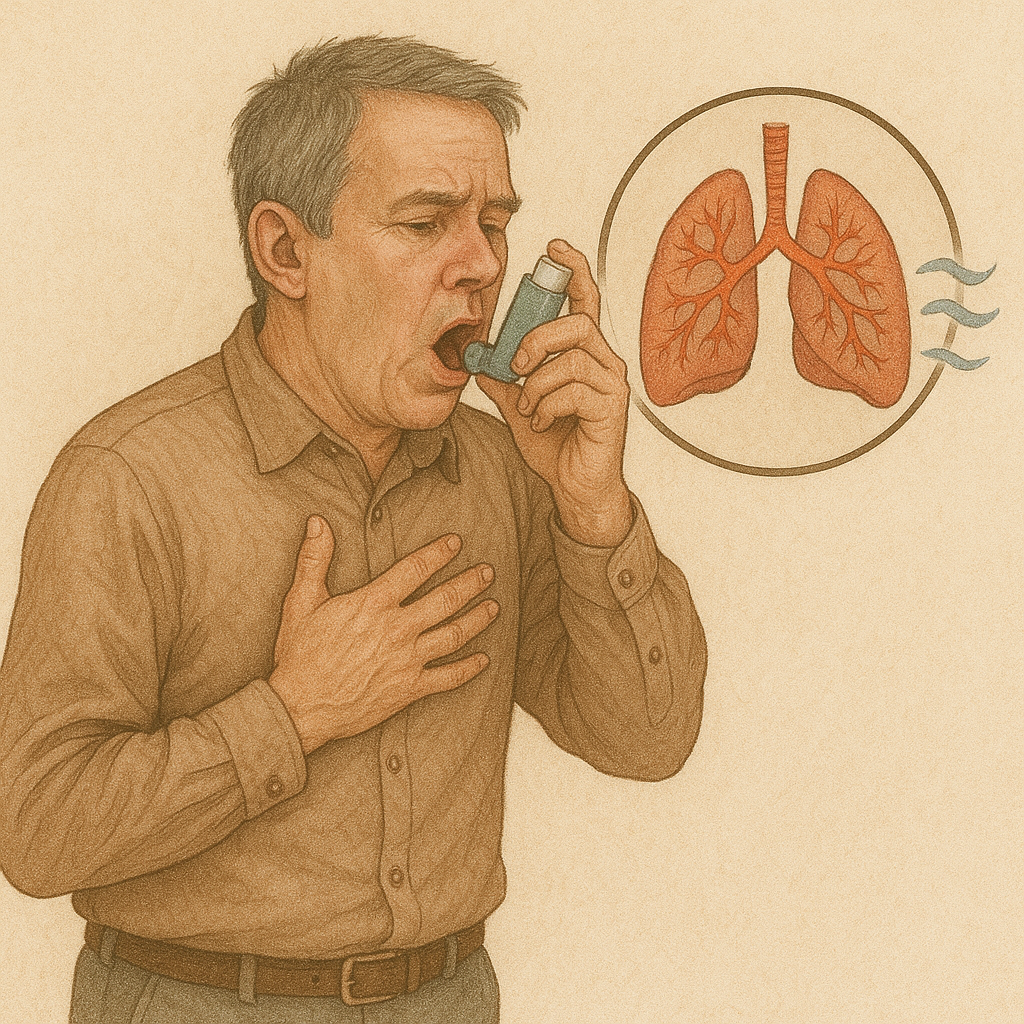

# Respiratory

Chronic Obstructive Pulmonary Disease (COPD)

क्रोनिक ऑब्स्ट्रक्टिव पल्मोनरी रोग (सीओपीडी)